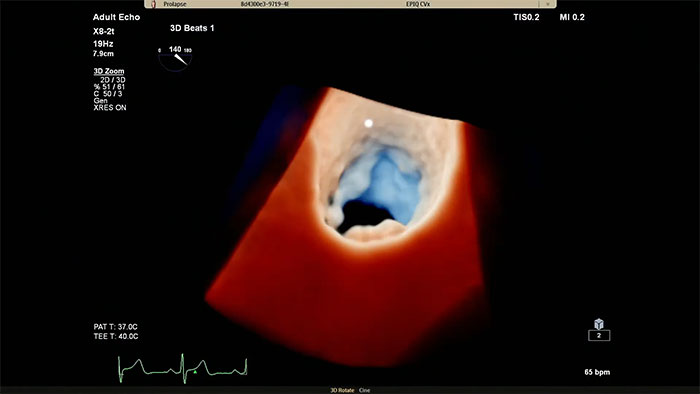

Philips Cardiac TrueVue on EPIQ CVx.

View enhanced visualizations of structures and flow with TrueVue Color

Visualize cardiac morphology using ultrasound with TrueVue Glass